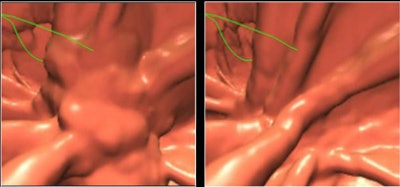

| Images show CTC data before and after electronic cleansing. All images courtesy of Hiro Yoshida, Ph.D. |